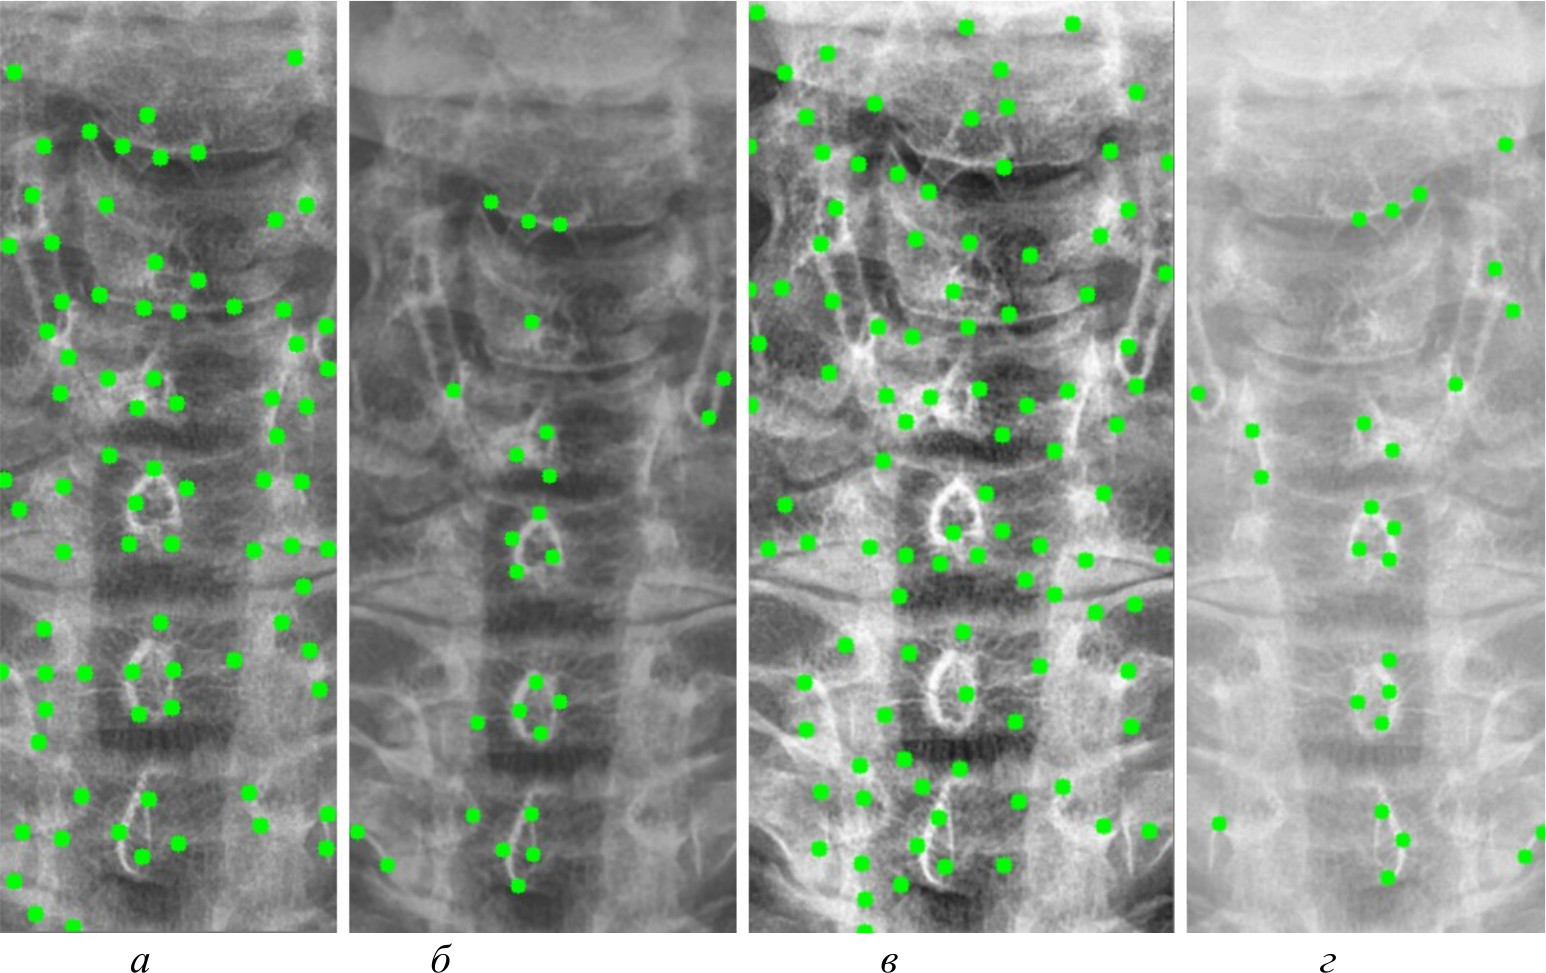

На рис. 4, 5 и 6 представлены результаты работы детектора Харриса, алгоритма Shi-Tomasi и SIFT при различных методах предварительной обработки изображений.

Рис. 4. Результаты работы детектора Harris на изображении, полученном при помощи специализированного программного обеспечения (а); результаты работы детектора Harris при методе адаптивной эквализации гистограммы (б); результаты работы детектора Harris при методе стандартной эквализации гистограммы (в); результаты работы детектора Harris при методе гамма-коррекции (г)

Рис. 5. Результаты работы алгоритма Shi-Tomasi на изображении, полученном при помощи специализированного программного обеспечения (а); результаты работы алгоритма Shi-Tomasi при методе базового отображения в Python (б); результаты работы алгоритма Shi-Tomasi при методе базового отображения Python с применением медианного фильтра (в); результаты работы алгоритма Shi-Tomasi при методе адаптивной эквализации гистограммы (г); результаты работы алгоритма Shi-Tomasi при методе стандартной эквализации гистограммы (д); результаты работы алгоритма Shi-Tomasi при методе гамма-коррекции (е)

Рис. 6. Результаты работы алгоритма SIFT на изображении, полученном при помощи специализированного программного обеспечения (а); результаты работы алгоритма SIFT при методе адаптивной эквализации гистограммы (б); результаты работы алгоритма SIFT при методе стандартной эквализации гистограммы (в)

После получения всех карт анатомических ориентиров составлена таблица и проведен сравнительный анализ. В таблице представлены данные сравнительного анализа методов предварительной обработки и алгоритмов распознавания анатомических ориентиров. В ней представлены следующие данные:

Метод | Принцип | Количество анатомических ориентиров (кластеров) и распределение по ним | Точность | Точность до обработки | ||

Harris | Shi-Tomasi | SIFT | ||||

Программа Dicom Image Viewer (эталон) | PNG-картинка полученная, специализированным программным обеспечением | 78 кластеров 6: 8, 15, 13, 14, 15, 13 | 80 кластеров 6: 8, 15, 15, 13, 14, 16 | 40 кластеров 4: 9, 15, 11, 6 | Harris – 87 %, Shi-Tomasi – 90 %, SIFT – 78 % | Harris – 65 %, Shi-Tomasi – 68 %, SIFT – 54 % |

Базовое отображение Python (Pillow) | Отображение при помощи библиотеки Pillow в Python | Не нашел | 80 Кластеров 6: 10, 10, 17, 15, 13, 15 | Не нашел | Shi-Tomasi – 45 % | Shi-Tomasi – 25 % |

Медианный фильтр | Отображение при помощи библиотеки Pillow в Python с применением фильтра Гаусса и медианного фильтра | Не нашел | 80 Кластеров 6: 8, 15, 11, 17, 14, 15 | Не нашел | Shi-Tomasi – 35 % | Shi-Tomasi – 22 % |

Адаптивная эквализация | Разбитие снимка на небольшие области и контрастирование каждой из них с применением фильтра Гаусса и медианного фильтра | 26 кластеров 6: 3, 1, 6, 4, 5, 7 | 80 кластеров 6: 4, 12, 17, 14, 12, 21 | 38 кластеров 6: 1, 4, 9, 10, 11, 3 | Harris – 77 %, Shi-Tomasi – 82 %, SIFT – 74 % | Harris – 65 %, Shi-Tomasi – 71 %, SIFT – 62 % |

Стандратная эквализация | Перераспределение значения пикселей для их равномерного распределения по диапазону. Данный метод выявляет более мелкие детали на изображении | 50 кластеров 6: 6, 8, 10, 8, 5, 10 | 80 кластеров 6: 8, 16, 16, 14, 10, 16 | 37 кластеров 6: 4, 8, 8, 9, 5, 3 | Harris – 91 %, Shi-Tomasi – 95 %, SIFT – 87 % | Harris – 74 %, Shi-Tomasi – 78 %, SIFT – 71 % |

Гамма-корректировка | Отображение при помощи библиотеки Pillow в Python с применением фильтра гамма-коррекции | 26 кластеров 6: 4, 2, 6, 4, 4, 6 | 80 Кластеров 6: 8, 15, 17, 12, 12, 16 | Не нашел | Harris – 55 %, Shi-Tomasi – 65 % | Harris – 38 %, Shi-Tomasi – 47 % |

Максимальное количество кластеров, которое может быть выделено, равно 6, так как на рентгеновских снимках выделялась часть спины, включающая 6 позвонков. Некоторые методы выделяют меньше кластеров, в то время как другие – больше; кроме того, часть методов не смогла распознать ключевые анатомические ориентиры вовсе. Это связано с особенностями алгоритмов и качеством предварительной обработки изображений.

На рис. 7 представлена гистограмма, на которой представлено количество ключевых анатомических ориентиров, распознанных при помощи трех алгоритмов на различных предварительно обработанных изображениях.

Рис. 7. Гистограмма сравнительного анализа методов предварительной обработки и алгоритмов распознавания ключевых анатомических ориентиров

Из данных таблицы видно, что наилучшим алгоритмом распознавания анатомических ориентиров является алгоритм Shi-Tomasi. Он распознал максимальное количество анатомических ориентиров вне зависимости от качества изображения, с которым работал, в то время как детектор Harris и алгоритм SIFT не смогли их распознать на изображениях, полученных при помощи базового отображения библиотекой Pillow, а также при применении медианного фильтра. Также алгоритм SIFT не смог найти ориентиры на изображении, полученном при гамма-коррекции.

Проанализировав все методы предварительной обработки и то, как алгоритмы смогли распознать ключевые анатомические ориентиры на них, можно сделать несколько выводов. Наилучшим методом оказалась стандартная эквализация изображений, при которой алгоритм Shi-Tomasi распознавал анатомические ориентиры с точностью около 95 %. Использование специализированного программного обеспечения также показало неплохие результаты, но немного уступало стандартной эквализации по точности распознавания – около 90 %. Остальные методы, такие как применение фильтров или гамма-коррекция, показали более низкую точность, в диапазоне от 35 до 75 %. В свою очередь, применение любого метода предварительной обработки повышало точность распознавания ключевых анатомических ориентиров на 15–25 %. В итоге наиболее предпочтительными методами оказались стандартная эквализация и специализированное программное обеспечение.